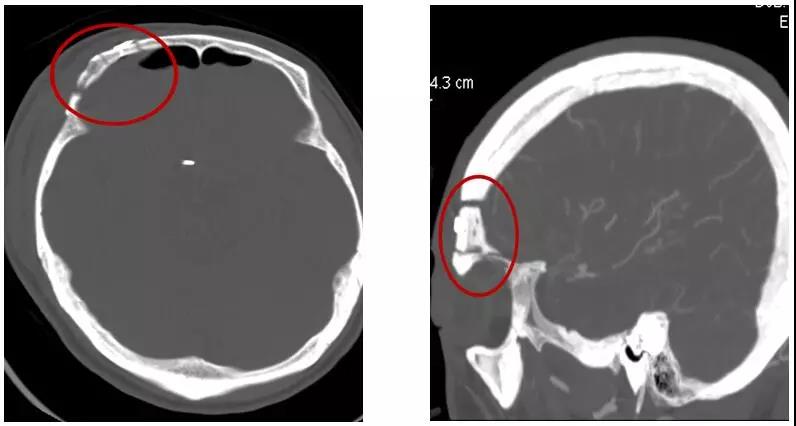

術(shù)中切口及骨瓣

據(jù)悉,按照以往的手術(shù)方式,賴先生需要在額顳部開一個長達15-20厘米左右的切口。手術(shù)創(chuàng)傷和風險大,且住院時間長,花費高。如今,惠州三院神經(jīng)外科開展了眉弓鎖孔入路這項技術(shù),只需在眉弓上緣開一長約5厘米左右的切口就能完全夾閉動脈瘤。既完整切除了病灶,又避免了普通開顱手術(shù)對患者外觀與容貌的影響。

它根據(jù)每個患者的具體情況,準確設計開顱部位和范圍,充分利用腦組織的自然間隙,以最短的手術(shù)路徑精確到達病變,將手術(shù)創(chuàng)傷降至最低。然而,這項技術(shù)對術(shù)者的要求很高,必須具備扎實的神經(jīng)解剖生理基礎和精湛的顯微手術(shù)基本功。